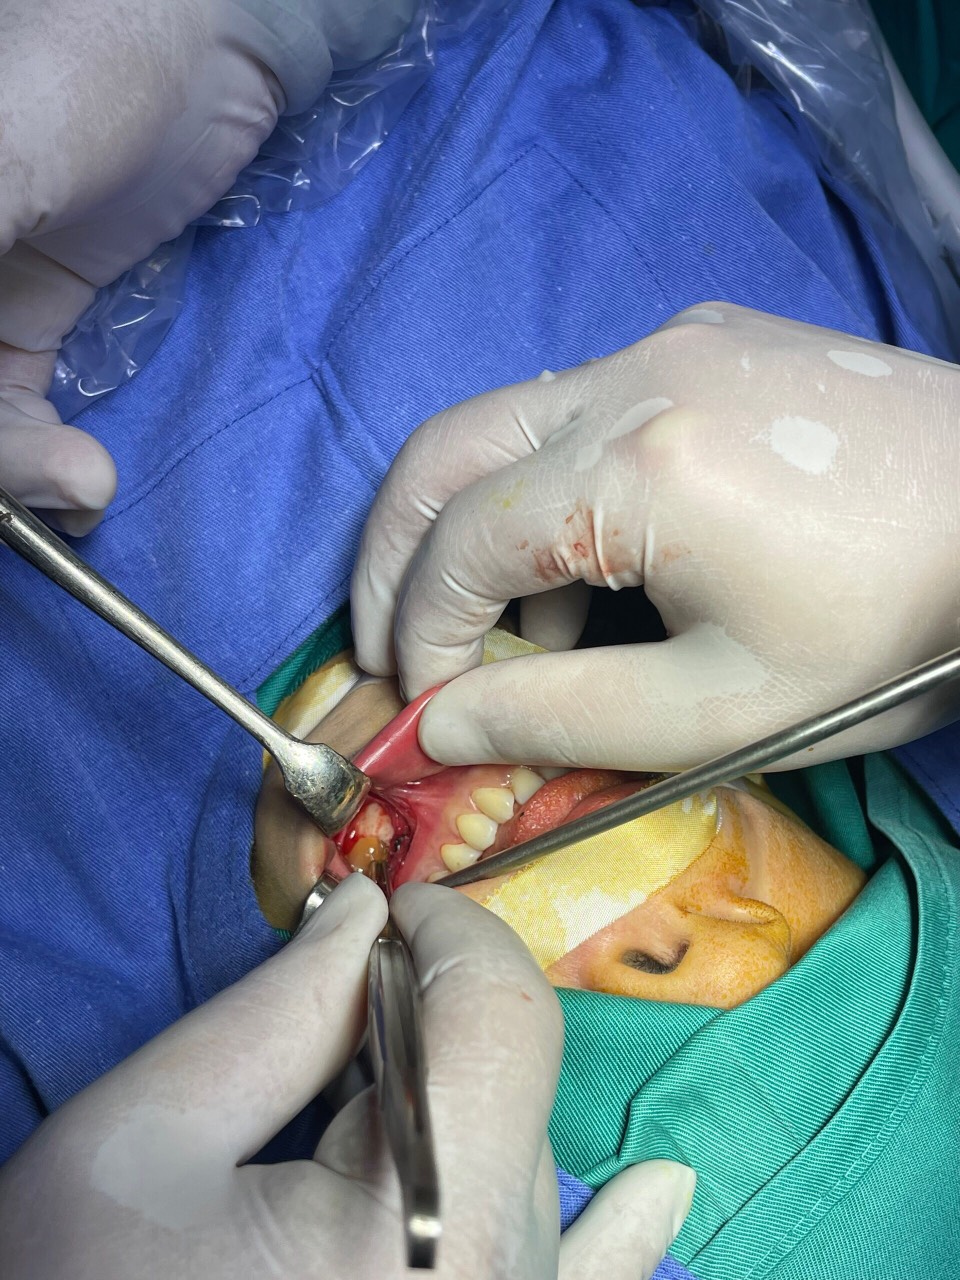

Hình ảnh trước phuẫu thuật của BN

Khoa Răng hàm mặt - Mắt - Tai mũi họng - Gây mê hồi sức vừa thực hiện thành công ca phẫu thuật cắt nang chân răng kết hợp huyết tương giàu tiểu cầu cho bệnh nhân H.T. Đ (Hùng Mỹ).